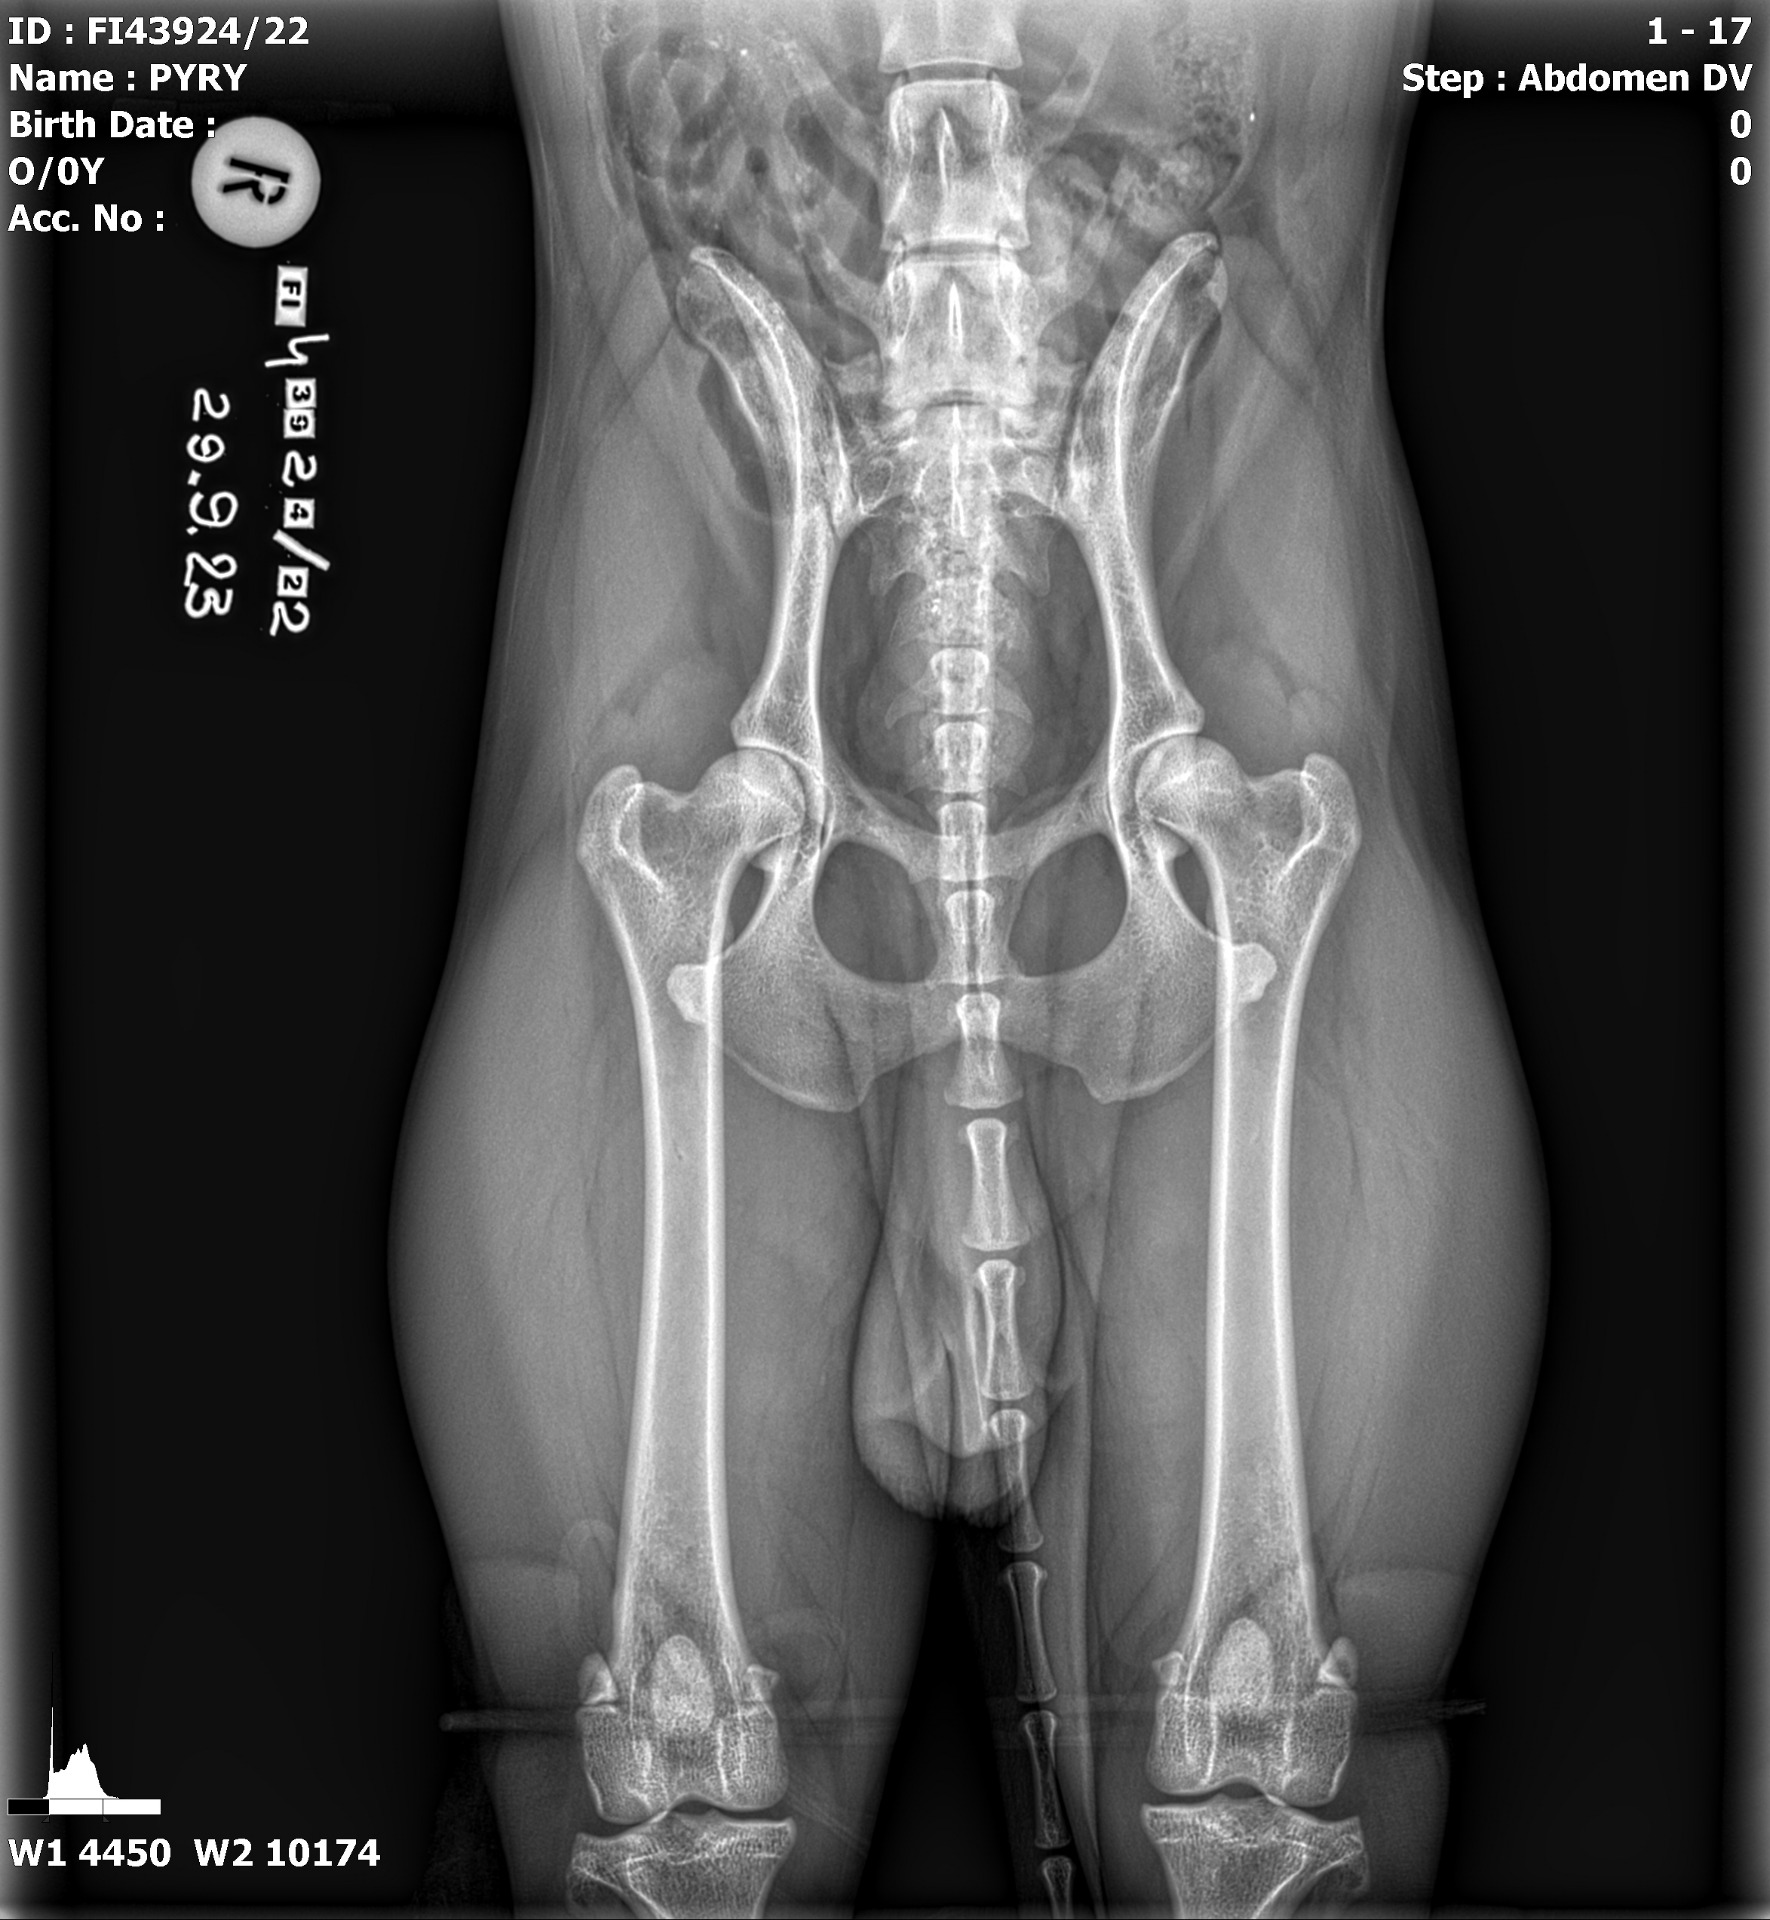

Lisää kasvatteja on käynyt luustokuvilla hyvin tuloksin: Pyry ja Loci saivat priimatulokset ja molemmilla siis lonkat A/A, kyynäret 0/0, selkä LTV0 (Locilla myös VA0-lausunto) ja olat terve/terve. Mallalla muutoin samanlainen rivi, mutta selässä LTV1 VA0. Myös kasvuiässä ollut toisen olan tulkinnanvarainen muutos on siis kokonaan hävinnyt. Mahtavaa!

Myös tuontikoira Texas kävi luustokuvilla ja raportoin tässä nyt senkin, vaikka kivesvian jalostuskäyttöä sille ei olisi ollut tulossa joka tapauksessa. Texasilla lonkat C/C, kyynäret 0/0, selkä LTV0 VA0 ja olat terve/terve. Lonkat näytti ainakin omaan silmään aika lieviltä, kuvannutkin eläinlääkäri oli pitänyt niitä hyvinä. Koiran kannalta ajateltuna ei siis C:n skaalan huonoimmassa päässä, vaan lonkkamaljan pienen mataluuden ja löysyyden vuoksi mennyt B:stä C:ksi. Toivon ja uskon, että lonkat ei tule Texasia vaivaamaan. Ikävä yllätys tämä kyllä oli sekä meille, että kasvattajallekin, koska emän ja isän sisaruksissa on tervettä lonkkaa, samoin kuin emän edellisessä pentueessa. Mutta ainahan näitä voi silti tulla. Jalostustoimikunta-aikanani keräsin joskus tilastoa siitä millaisia yhdistelmiä lonkkanivelten ja siis erityisesti vanhempien lonkkanivel-indeksien suhteen oli tehty tiettynä ajanjaksona, ja millaisia lonkkaniveltuloksia jälkeläisille tuli. Kyllähän siitäkin näkee, että joskus huono arpaonni osuu kohdalle vaikka ennustearvo olisi hyvään lonkkaan. Siksikin täytyy olla aina erityisen tyytyväinen, jos kasvattien tulokset on hyviä, vaikka siihen olisikin valinnoilla pyritty. Toisaalta tämä myös osoittaa sen, mikä merkitys on lonkkanivelindekseillä ja että niitäkin kannattaa huomioida optimoidakseen mahdollisuuden saada lonkiltaan terveitä jälkeläisiä. Toistaiseksi omat valinnat näyttää menneen hyvin ja toivon, että sama linja jatkuu.